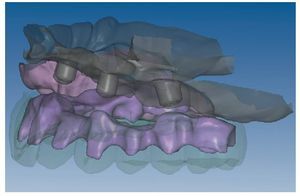

Mediante el uso de un escáner óptico de luz estructurada, los protocolos CAD registran los primeros datos relativos al modelo maestro con las correspondientes posiciones de implante (figs. 87 y 92). En el siguiente paso tiene lugar la digitalización de la planificación, previamente realizada en cera de escaneo matificada, de la restauración definitiva (figs. 88, 90 y 93). La subsiguiente conciliación de los datos mediante el uso del software de diseño dental permite al protésico planificar virtualmente el resto del procedimiento (figs. 89 y 91, 94 a 96) a partir del diseño de las estructuras (figs. 97 y 98).

Fig. 92. Imagen CAD del modelo maestro del maxilar inferior.

Fig. 93. Imagen CAD de la planificación definitiva para el maxilar inferior.

Figs. 94 a 95. Planificación CAD de la estructura del maxilar inferior, en representación lingual y vestibular.

Figs. 96 a 98. El diseño definitivo de la estructura del maxilar inferior, desde distintas perspectivas.